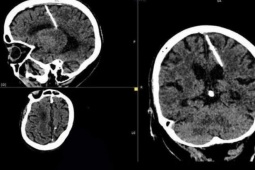

Đang ngủ, bé gái 13 tuổi suýt đột tử vì mắc bệnh hiếm gặp

Trước khi nhập viện, gia đình phát hiện bệnh nhi có hai cơn co gồng, tím môi khi đang ngủ.